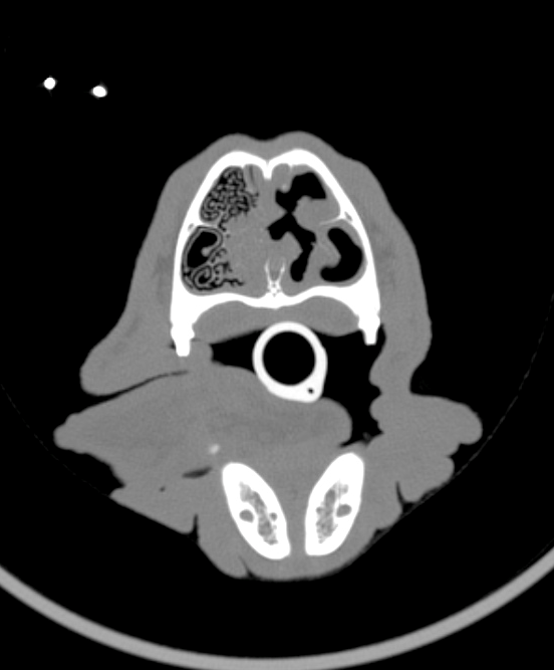

What is the issue here?

Aspergillosis into frontal sinuses